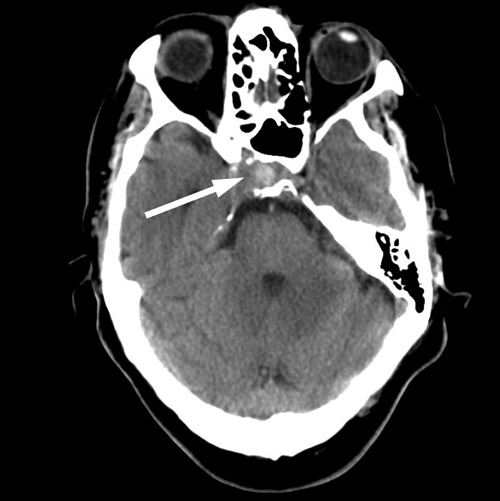

Dagen etter transsfenoidal prøvetaking i narkose fikk pasienten akutt forverring av hodepinen, og det ble tatt en ny cerebral CT og CT-angiografi (fig 4). Den viste at den patologiske prosessen i sfenoidalsinus hadde ekspandert og at aneurismet hadde økt i størrelse til 16 mm i diameter.

Den akutte forverringen av smertene skyldtes sannsynligvis en størrelsesøkning av aneurismet og derved påvirkning av nervestrukturer i sinus cavernosus. Vi ble nå overbevist om at pasienten hadde en infeksiøs prosess med utgangspunkt i sfenoidalsinus som destruerte a. carotis interna og ga et pseudoaneurisme. Det forelå absolutt indikasjon for å eliminere aneurismetilstanden for å forhindre en katastrofal epistaxis. På grunn av den pågående infeksjonen og sannsynlig pseudoaneurisme fant vi det ikke mulig å gjennomføre coilbehandling bak stent i det infiserte området. Det ble vurdert å gjøre eliminasjon av aneurismet ved «trap ligation», det vil si avstengning av a. carotis interna både proksimalt og distalt for aneurismet på den aktuelle høyre siden. Dette forutsatte at pasientens høyre hjernehalvdel kunne få tilfredsstillende tilførsel fra venstre a. carotis interna.

Arteriell cerebral angiografi med kontrastinjeksjon på venstre side og kompresjon av a. carotis interna på høyre side viste at det ikke var overgang av blod fra venstre carotis til høyre hjernehalvdel via a. communicans anterior. Pasienten ville derfor ikke tåle okklusjon av a. carotis interna på den aktuelle høyre siden. Transkranial doppler bekreftet disse funnene. Videre viste arteriell angiografi at aneurismet var blitt dobbelt så stort på tre døgn (fig 5).